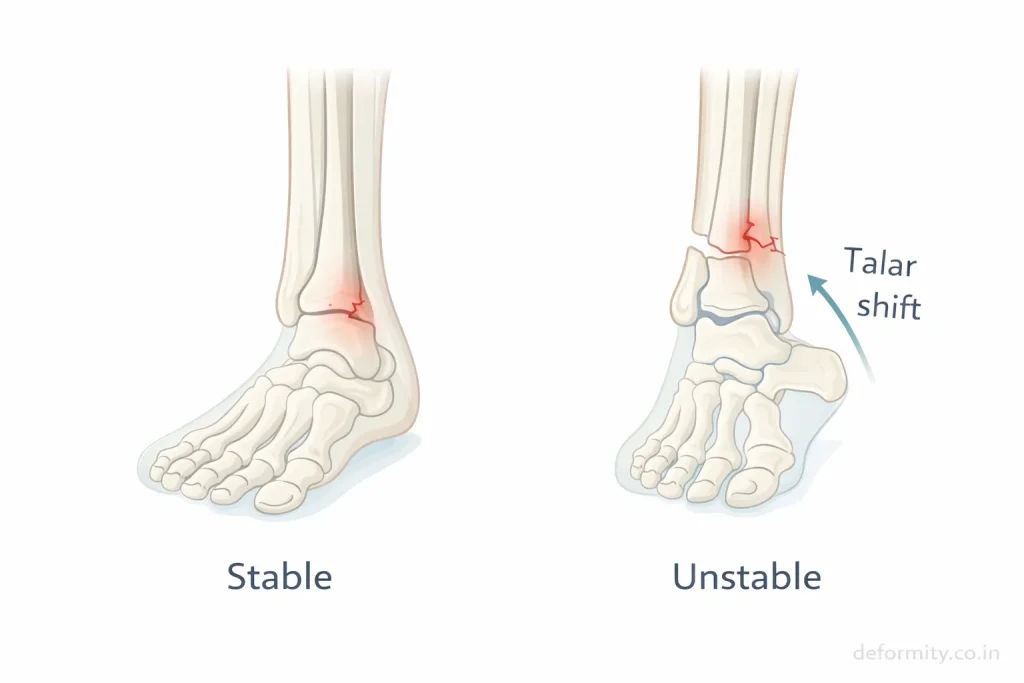

Stable vs Unstable Lateral Malleolus Fracture

The most important factor in treatment planning is stability.

A fracture is stable if:

- Bone alignment maintained

- No talar shift

- Ligaments intact

A fracture is unstable if:

- Bone displaced

- Syndesmotic injury present

- Associated medial malleolus fracture

- Joint misalignment

Stable fractures can heal with casting or boot immobilization, while unstable fractures usually require surgical fixation.